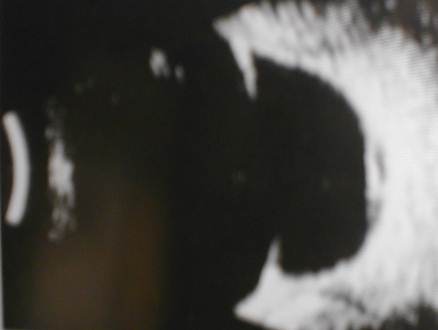

Of the three B scans above can

you differentiate asteroid hyalosis from vitreous haemorrhage?

The scans usually show white opacities

within the vitreous cavity. The main differential

diagnosis being : vitreous haemorrhage,

asteroid hyalosis and synchysis scintillans.

-

The three may look similar on the ultrasound

but in the case of vitreous haemorrhage they

may be associated posterior vitreous

detachment or retinal tear.